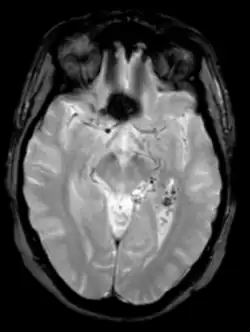

Magnetresonanztomographie/-angiographie

Die Auflösung der Bilder ist bei der Magnetresonanztomographie (MRT) oder Magnetresonanzangiographie (MRA) etwas höher und damit genauer. Vor allem Begleitveränderungen der AVM können besser dargestellt werden.[7] Das Verfahren arbeitet mit sich verändernden Magnetfeldern ohne Strahlenbelastung für den Patienten und ist damit als sicherere Methode anerkannt. Da es keine Strahlenbelastung gibt, wird die MRT auch bevorzugt bei regelmäßigen AVM-Nachsorgeuntersuchungen nach einer Behandlung eingesetzt. Die Untersuchungen dauern meist länger, teilweise bis zu einer Stunde. Auch bei der MRT können die Blutgefäße durch die gezielte Gabe von Kontrastmittel besser dargestellt werden.